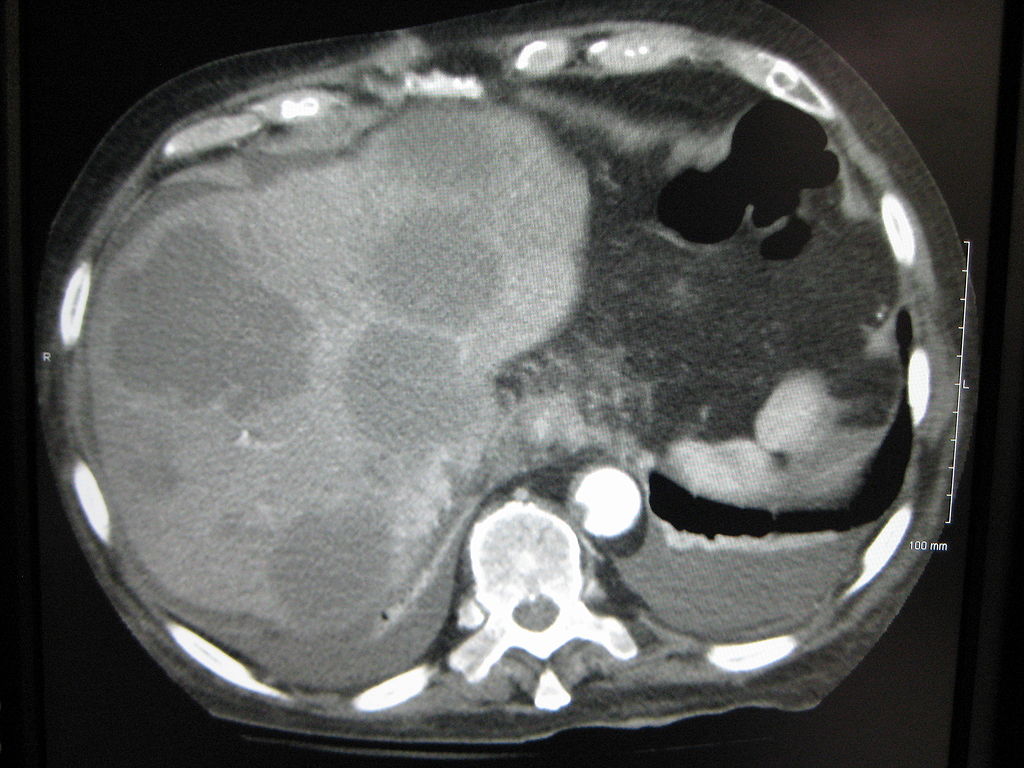

Axial CT of the abdomen showing multiple liver metastases. Image courtesy of James Heilman, MD / Wikimedia Commons / CC-BY-SA-3.0 |

The majority of liver metastases present as multiple tumors. Only 10% of all cases present with a solitary metastatic lesion. Moreover, in more than three-quarters (3/4) of patients with liver metastases, there is involvement of both lobes of the liver.